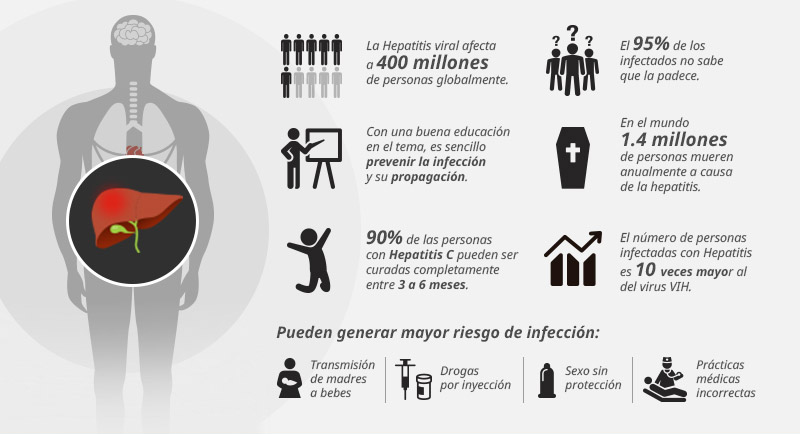

La hepatitis es una enfermedad terrible, no sólo por el profundo deterioro que causa al hígado y que podría provocar la muerte, sino porque se trata de una epidemia silenciosa que muchas veces no presenta síntomas, sino hasta que no hay nada más qué hacer.

Con el paso del tiempo, esta enfermedad viral que afecta a más de 400 millones de personas en el mundo, puede degenerar en cirrosis o en cáncer de hígado y culminar con la muerte de quien la padece.

Datos